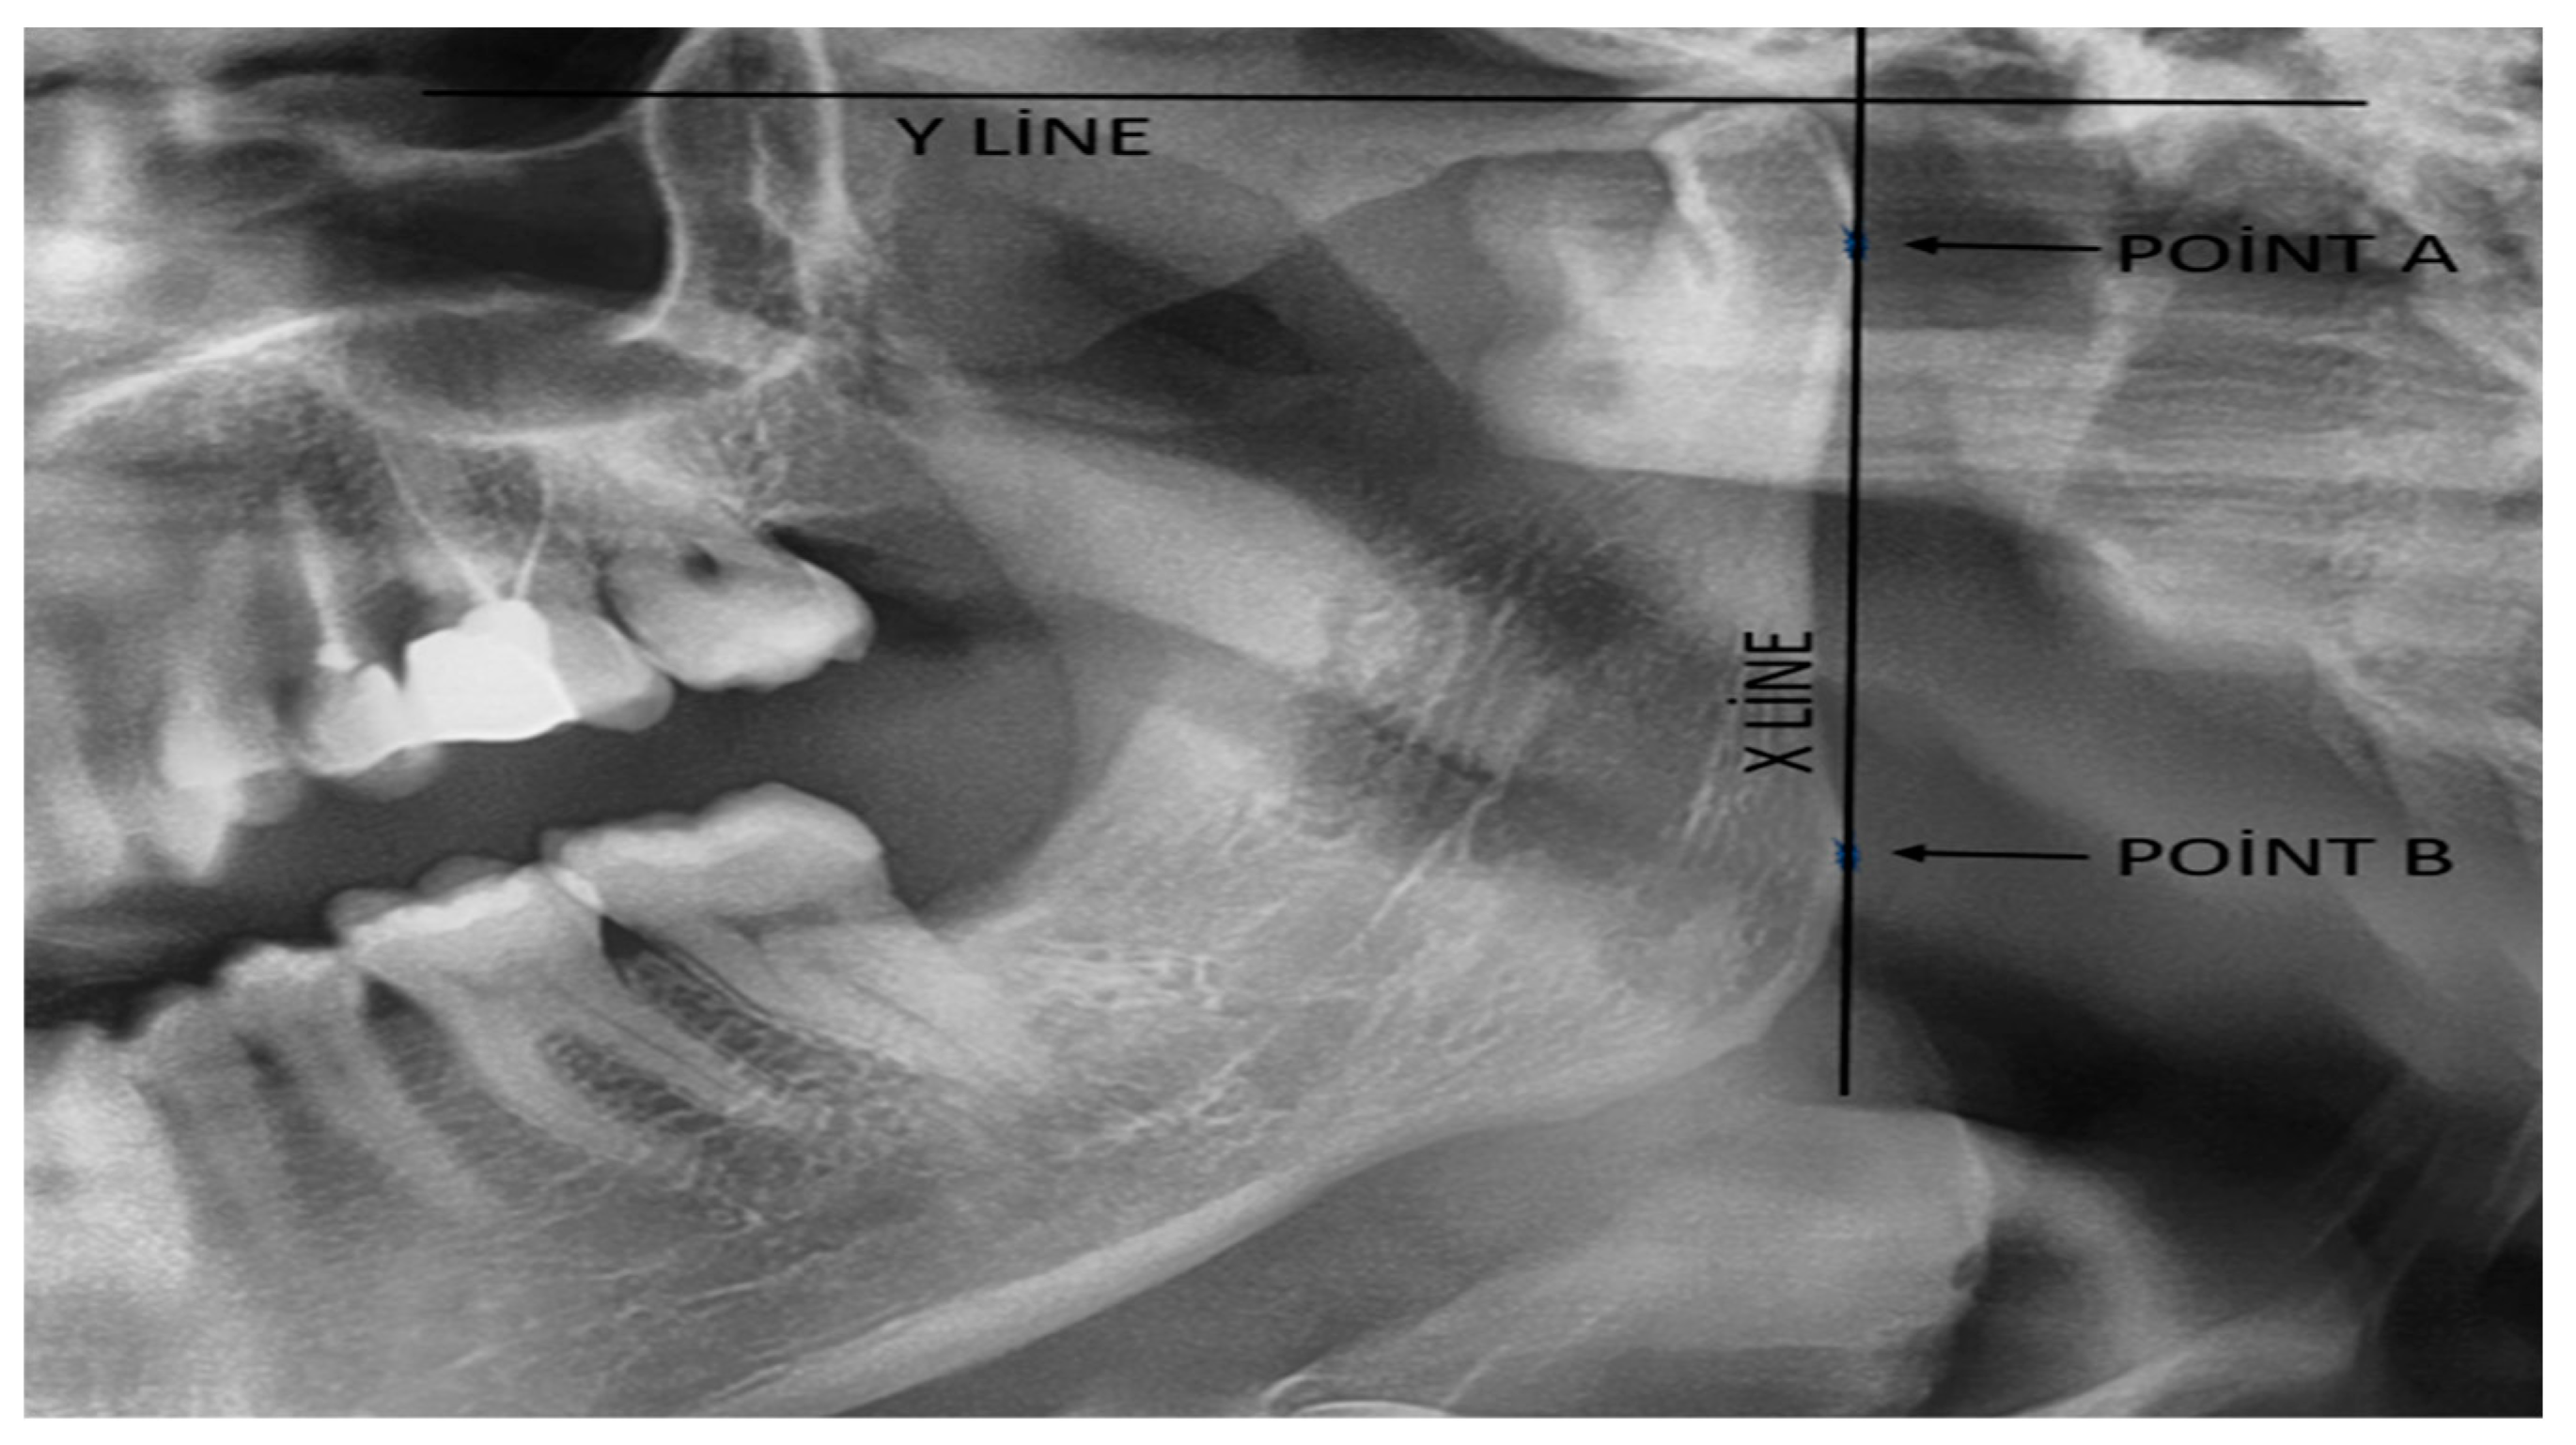

| CH: | Condyle Height |

| RH: | Ramal Height |

| CAI: | Condylar Asymmetry Index |

| RAI: | Ramal Asymmetry Index |